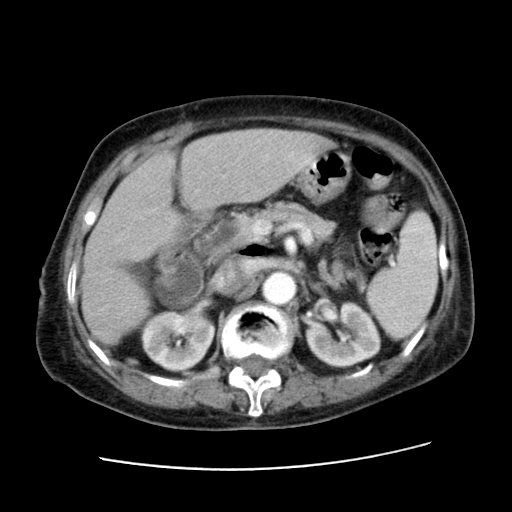

标题: CT25203:上腹部增强,看看

女,77.无不适

肝脏变异、异位胆囊,肝右叶肝内胆管结石并肝内胆管扩张。

肝右叶肝内胆管结石并肝内胆管扩张。

肝右叶肝内胆管结石并肝内胆管扩张

胆总管扩张

肝右叶肝内胆管结石并肝内胆管扩张。胆总管下段梗阻,考虑壶腹部占位。

右侧肝内胆管局限性扩张,其内密度不均匀,扩张的胆管壁增厚,考虑肝内胆管炎合并结石可能性大

肝右叶肝内胆管结石并肝内胆管扩张。胆总管下段梗阻,考虑壶腹部占位。支持